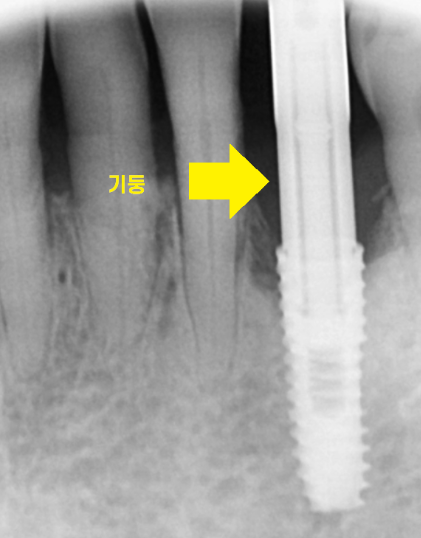

24.04.16

x-ray 상에서도 잇몸이 많이 녹아있네요ㅠㅠ

잇몸뼈가 많이 녹아

치아 뿌리만 겨우 붙잡고 있습니다.

붙잡고 있는게 얼마 없어

식사할때마다 흔들렸을꺼고

많이 불편하셨겠어요~